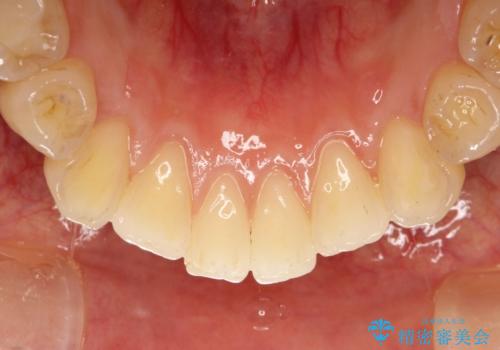

PMTCというクリーニングを行うことでステインは除去できるので、今回はPMTC(エアフロー)の60分コースにて全体のクリーニングを行いました。

エアフローは歯と歯の間や、詰め物との境目などブラシやチップが届かないところまで細かくお掃除が可能になります。

隅々までお掃除することで虫歯や歯周病のリスクを下げる効果があります。